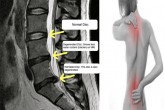

നടുവേദനയും പരിഹാരങ്ങളും

16 January 2017

മനുഷ്യശരീരത്തിലെ ഏറ്റവും പ്രധാനപ്പെട്ട അവയവമാണ് നട്ടെല്ല്. കശേരുക്കള്, ഡിസ്കുകള്, പേശികള്, സ്നായുക്കള്, ചലനവള്ളികള് തുടങ്ങിയവയാലാണ് നട്ടെല്ല് നിര്മിച്ചിരിക്കുന്നത്. നട്ടെല്ലിന്റെ അടിസ്ഥാന ഘടകം...